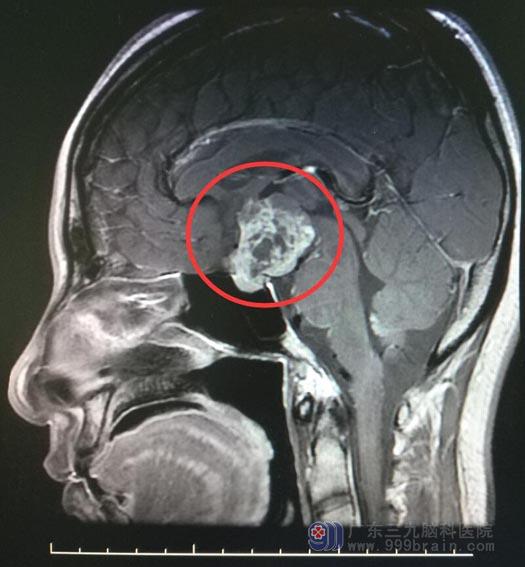

术前MR